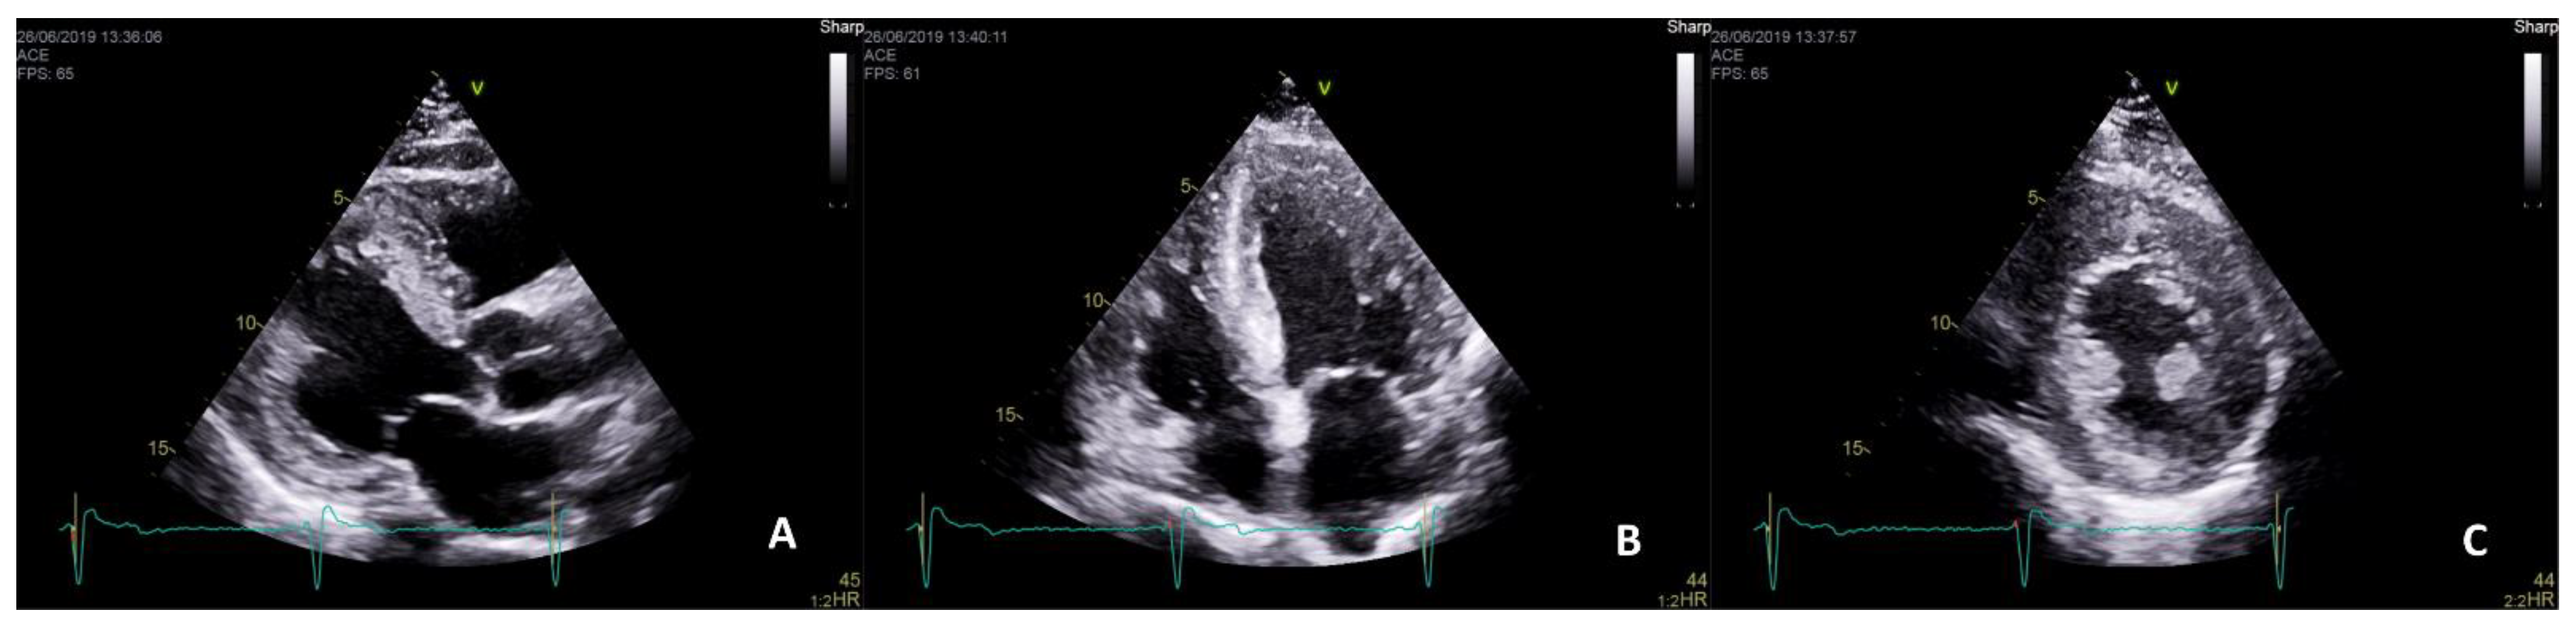

- Pieroni, M.; Chimenti, C.; De Cobelli, F.; Morgante, E.; Del Maschio, A.; Gaudio, C.; Russo, M.A.; Frustaci, A. Fabry’s Disease Cardiomyopathy: Echocardiographic detection of endomyocardial glycosphingolipid compartmentalization. J. Am. Coll. Cardiol. 2006, 47, 1663–1671. [Google Scholar] [CrossRef]

- Mundigler, G.; Gaggl, M.; Heinze, G.; Graf, S.; Zehetgruber, M.; Lajic, N.; Voigtländer, T.; Mannhalter, C.; Sunder-Plassmann, R.; Paschke, E.; et al. The endocardial binary appearance (’binary sign’) is an unreliable marker for echocardiographic detection of Fabry disease in patients with left ventricular hypertrophy. Eur. J. Echocardiogr. 2011, 12. [Google Scholar] [CrossRef][Green Version]

- Niemann, M.; Liu, D.; Hu, K.; Herrmann, S.; Breunig, F.; Strotmann, J.; Störk, S.; Voelker, W.; Ertl, G.; Wanner, C.; et al. Prominent Papillary Muscles in Fabry Disease: A Diagnostic Marker? Ultrasound Med. Biol. 2011, 37, 37–43. [Google Scholar] [CrossRef]